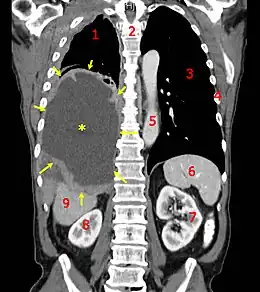

Cela se fait par la clinique (l'examen du patient) : palpation des seins, toucher rectal, etc. et des examens paracliniques (scanner, IRM, tomographie optique ou parfois échographie). Certains dépistages ont prouvé leur intérêt en diminuant le nombre de décès par cancer : le frottis du col utérin, pour dépister les lésions précancéreuses et les petits cancers du col utérin et les examens colorectaux. La mammographie, pour dépister des cancers du sein à un stade précoce, a fait l'objet de plusieurs controverses, en raison d'un fort accroissement des faux-positifs dans la population de moins de 50 ans, et il existe un consensus pour ne la pratiquer de façon systématique qu'au-delà de cet âge[193]. Pour autant, si tous les acteurs en rejettent l'idée avant 50 ans, tous n'adhèrent pas au principe d'un dépistage systématique après cet âge[194].